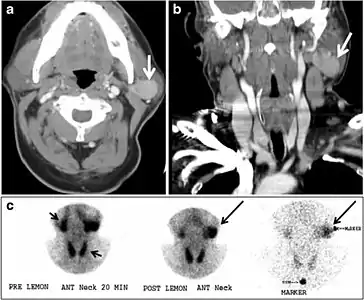

Fig. 17. Ectopic thyroid on the left parotid gland with a palpable left parotid mass in a 69-year-old male patient. a, b Axial and coronal enhanced neck CT scan demonstrates well-defined homogeneous enhancing mass (white arrows) within the left parotid gland with preserved surrounding fat planes. It also shows a normal thyroid in normal position in the lower neck. c Image taken 20 minutes after 5 mCi injected Tc99m-Pertechnetate shows normal thyroid uptake of tracer and physiological uptake in the salivary glands (short black arrow). There is a distinct focus of abnormal tracer accumulation in the left parotid/submandibular region. Patient was given lemon juice with evident normal washout from the salivary glands and relative retention by this abnormal focus (long black arrow).[1]

Fig. 18. Lingular thyroid in a 33-year-old male who presented with oropharyngeal bleeding. an Axial enhanced neck CT scan at the level of mandible demonstrates a 3 × 3 × 3.4 cm round, partly well-delineated, heterogeneously enhancing lesion (white arrow). It is predominantly on the left side of the oropharynx and to some extent at the mid part of the base of the tongue. The thyroid gland was normal (not shown). b Image of the anterior face and neck taken 20 minutes after Tc99m-Pertechnetate injection shows absent thyroid radiotracer uptake in normal thyroid anatomical location (black short arrows). There is an area of increased uptake (long black arrows) corresponding to the posterior tongue mass identified on CT scan.[1]